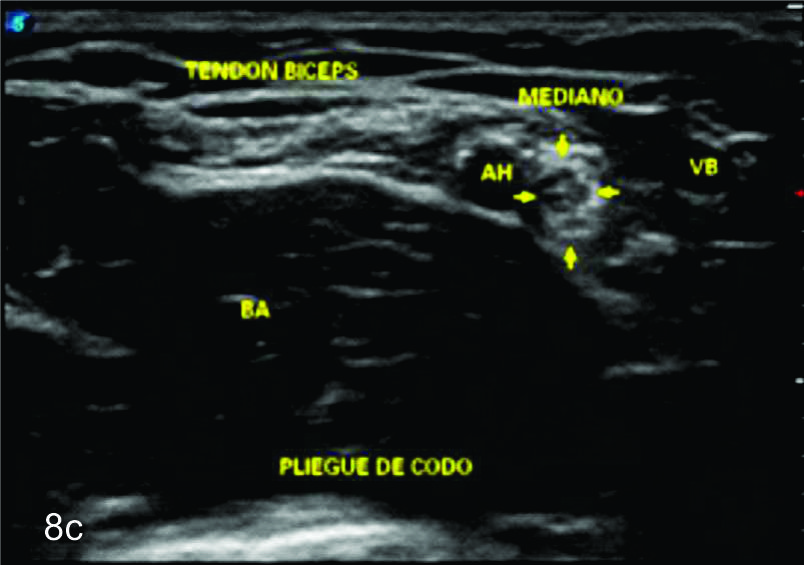

Figura 8

Nervio mediano

Serie de cortes axiales del nervio mediano desde su origen a nivel del hueco axilar hasta el sector distal del antebrazo previo a su ingreso al túnel del carpo. Se identifica el mismo señalado por flechas amarillas y con la palabra mediano. AA-arteria axilar, VA- vena axilar, AH- arteria humeral, VH- vena humeral, VB- vena basilar, AC- ateria cubital, VC- vena cubital, BA- músculo braquial anterior, PR- músculo pronador cuadrado, FS- músculo flexos superficial, FP- músculo flexor profundo, PC- músculo pronador cuadrado. A- axila, se identifica el nervio superfical a la arteria axilar, B- tercio medio del brazo en canal bicipital medial, lateral a la arteria humeral, C- codo, medial al tendón distal del bíceps braquial y a la arteria humeral luego de cruzarla, superficial al músculo braquial anterior, D-antebrazo sector cefálico, entre las dos cabezas del pronador redondo, E- tercio medio del antebrazo, entre los músculos flexor superficial y profundo F- tercio distal antebrazo, superficial al pronador cuadrado.